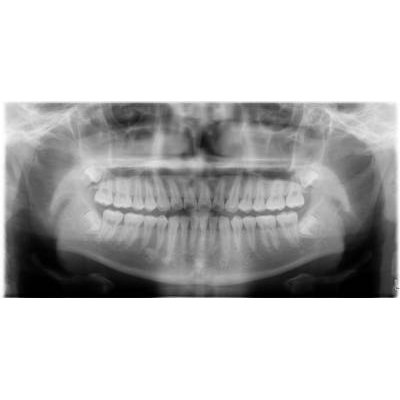

兒童牙科

人工植牙

商品大圖